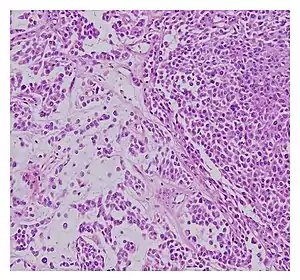

| Histopathological examination of malignant chondroid syringoma | |

Histologically, these malignant mixed tumours have epithelial and mesenchymal components and are very large, nodular, circumscribed, and nonulcerated.[9] They are morphologically identical to pleomorphic adenoma and have a female predilection.[4] They range from developing deep dermal to subcutaneous nodules and metastasise at a very high rate.[4][6] Malignant mixed tumours can emerge "de nova or more rarely develop from a cartilaginous syringoma."(IADVL, 2004)[9]